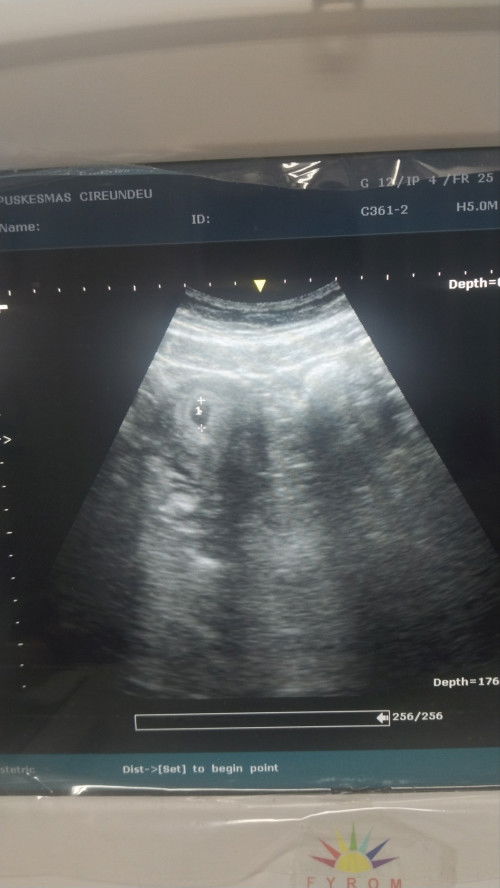

Yg pertama USG di puskesmas tgl 4/10/25 ke detek usia kandungan 5w6d karna baru keliatan kantungnya, tgl 6 nge flek akhirnya di rujuk ke obgyn. Tgl 7/10/25 USG transvaginal usia kandungan 5w3d turun 3 hari. Alhamdulillah kantungnya masih aman walau nge flek . Hari ini sama kmaren nge flek juga dikit. Disuruh kontrol lagi 2 Minggu kemudian . Doain ya bunda bunda semoga janinnya kuat kaya mamahnya.. semoga berkembang lengkap sesuai umurnya.. #Sharingdong_Bund #firstmom